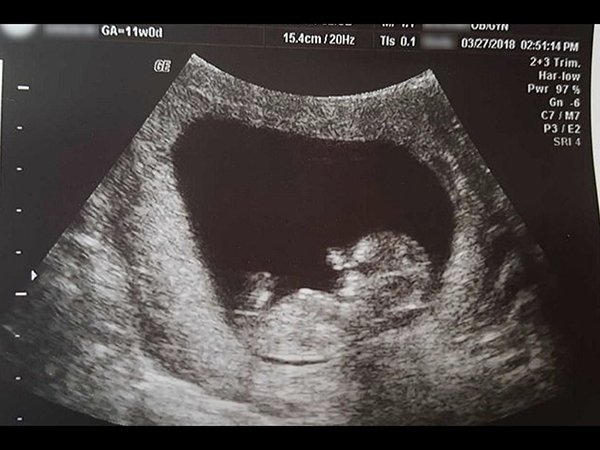

வயிற்றிலே கலைந்துபோன 14 வார குழந்தை கருவின் புகைப்படத்தை தைரியமாக வெளியிட்ட பெண்

தன்னுடைய கருவில் 14 வாரக் குழந்தை கலைந்து போனதை புகைப்படமாக வெளியிட்டிருக்கும் தைரியமான தாய் பற்றிய விஷயத்தைத் தான் நாம் இங்கே பார்க்கவிருக்கிறோம். அதுபற்றிய தொகுப்பும் புகைப்படங்களின் தொகுப்பும் தான்

தன் வயிற்றில் சுமந்து பெற்ற பிள்ளையை இழப்பதை விட பெரிய கொடுமை வேறு எதுவும் இல்லை. ஒரு பெண்ணின் வயிற்றில் கருவாக உருவான குழந்தை 14 வாரங்கள் ஆன நிலையில் அந்த குழந்தையை இழக்க வேண்டிய நிலை அந்த தாய்க்கு உருவானது. அந்த சோக கதையை அவர் நம்மிடம் பகிர்ந்து கொள்கிறார். மேலும் அந்த தைரியமான தாய் அந்த குழந்தையின் புகைப்படங்களையும் வெளியிட்டிருக்கிறார். இந்த புகைப்படங்களைக் காணும்போது இதயமே உடைந்து விடுகிறது. வாருங்கள் அதனை இப்போது பார்க்கலாம்..

இந்த கருவின் வளர்ச்சி வெறும் 14 வாரங்கள் மட்டுமே. ஆனால் துரதிர்ஷ்டவசமாக இந்த குழந்தையை கலைக்க வேண்டிய சூழ்நிலையில் கிறிஸ்டியன் ஷரன் என்னும் இந்த தாய் இருக்கிறார். இந்த புகைப்படங்களை இவர் பதிவிட்டதன் காரணம், இந்த குழந்தையின் உடல் முழுவதும் வளர்ச்சி பெற்ற நிலையில் இருக்கிறது என்பதை அனைவருக்கும் காண்பிக்கவே. ஆனால் இந்த குழந்தையின் மொத்த எடை 0.05பவுண்ட். மற்றும் இதன் நீளம் 4 இன்ச் மட்டுமே.